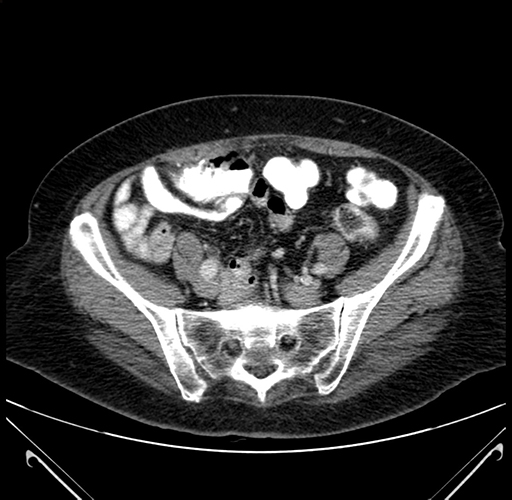

Axial Venous

Coronal Venous